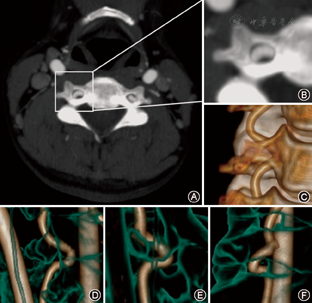

所有患者均经过GE LightSPeed VCT 64排双能CT或者PhiliPs 256i CT进行颈椎增强CT扫描,将增强图像导入Philips IntelliSpace Portal工作站进行三维重建。选取观察组患者扭曲椎动脉相邻节段及对照组各节段的横突孔作为观测对象(图1),采用spline contour作为面积测量工具,在血管窗(窗宽800,窗位300)中测量椎动脉截面积(VA),在骨窗(窗宽1 500,窗位500)中测量横突孔面积(TF) (图2)。为评价单节段内椎动脉扭曲程度,采用屏幕E尺工具测量受试节段上侧横突孔下缘至下侧横突孔上缘的直线距离作为该段颈段长度,测量沿相应节段椎动脉走行所作的曲线长度作为该段椎动脉长度,以后者除以前者作为椎动脉扭曲系数(s)(图1)[5]。以上数据由两名受过培训的临床医师进行测量,数据取两者的均值。如出现两组数据相差超过较小值的5%,则重测数据。

在本研究对象中存在6例横突孔内椎动脉严重扭曲。这些均为老年患者,平均年龄为(75.2±5.6)岁,平均TF为(48.6±8.2) mm2,近正常TF的1.7倍,同时可以观察到横突孔扩大的趋势与扭曲椎动脉的走行相一致。这个发现支持了扭曲的椎动脉可以导致血流动力学改变,并对横突孔的骨性结构造成切割作用的推论[10,11]。骨组织受到相邻结构压迫可出现退行性改变和骨密度增生是已知的病理学现像[10],本研究观察到扭曲椎动脉压迫处横突孔内壁出现孔径扩大和骨密度增高,结合椎动脉扭曲与颈椎横突孔扩大有正相关的统计学结果,"椎动脉扭曲导致颈椎横突孔扩大"的结论符合病程发展的逻辑。但扩大的横突孔可提供更多空间容纳椎动脉迂曲其中,致使这两种病理形态互相促进。值得注意的是,椎动脉扭曲和盘旋对横突孔周围结构产生显著的破坏,在此类老年患者颈椎手术中更易于造成致命的手术并发症。因此对于椎动脉严重扭曲的患者进行手术应十分谨慎,尽可能术前进行详细的影像学检查和分析以制定个体化的螺钉植入方案。